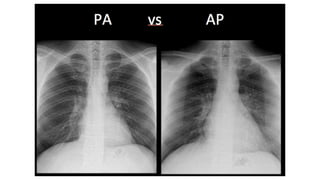

Chest x-ray in Congenital Heart disease

Chest x-ray inCongenital Heart disease